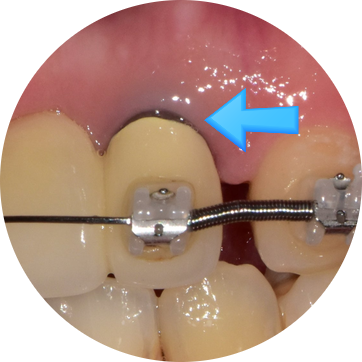

25.06.12 신경치료 마무리 후 크라운씌우기 직전 예시사진